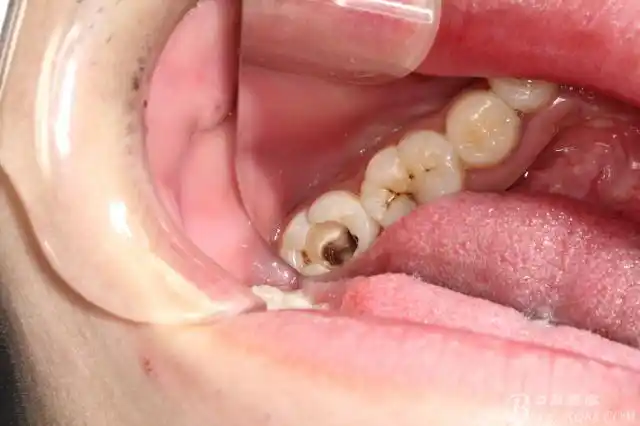

一例右下第二磨牙橡皮障与热牙胶的联合应用